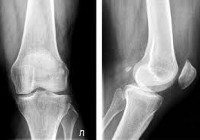

Рентген суставов. Метод лучевой диагностики, позволяющий выявлять патологические изменения в костных структурах и окружающих околосуставных тканях, а также отслеживать динамику изменений рентгенологических симптомов при различных заболеваниях. Рентгенологические признаки, указывающие на повреждение сустава, могут включать сужение или расширение суставного пространства, утолщение и затвердение мягких тканей, кальцификации, кистозное просветление костной ткани, эрозию суставных поверхностей, остеофитов, нарушение нормальных пространственных отношений между суставами. голова и полость ; Контрастная артрография, пневмоартрография, а также компьютерная и магнитно-резонансная томография суставов используются при диагностике ревматических заболеваний и травм наряду со стандартной рентгенографией суставов.

Основой рентгенографии суставов является способность тканей различной плотности поглощать различные количества рентгеновских лучей, плотная кость поглощает большое количество радиации, мягкие ткани - небольшое количество. Используя специальное устройство, рентгенолог направляет рентгеновский луч на сустав. Лучи проходят через ткань и образуют изображение на пленке за суставом. Костные структуры сустава имеют почти белый вид, мягкие ткани имеют различные оттенки темно-серого.

Совместная рентгенография в Москве широко используется в травматологии, ортопедии и ревматологии. Если указано, он используется в челюстно-лицевой хирургии, онкологии и в других областях медицины. Рентген суставов позволяет диагностировать переломы, переломы, вывихи, подвывихи, артрозы, артриты, врожденные аномалии развития, нарушения обмена веществ, доброкачественные и злокачественные примитивные опухоли и метастатические поражения суставных концов костей при различных онкологических заболеваниях. При введении атмосферных или контрастных агентов рентгенография суставов может использоваться для выявления патологии хрящей и мягких тканей (связок, менисков, суставных мешков).

Используя это исследование, можно определить количество, положение, степень и направление движения костных отломков при внутрисуставных и периартикулярных переломах, выявить нарушения конгруэнтности конечностей суставов при вывихах и подвывихах. Рентгенография суставов полезна для локального или диффузного уменьшения или увеличения плотности костей (остеопороз и остеосклероз), наличия внутрисуставной жидкости при гемартрозе и синовите, сужения суставного пространства при артрозе, расширения суставного пространства при разрыве связки.

Рентген суставов позволяет обнаруживать деформации суставов концов кости в результате остеоартрита, артрита или неправильно связанного перелома, а также выявлять краевые новообразования костей и очаги кальцификации в мягких тканях сустава (связка, капсула сустава, синовиальная оболочка, кожа, мышцы и ). жировая ткань). Кроме того, при исследовании рентгеновских лучей вы можете увидеть опухоли, расположенные в костях (если смотреть детально, вы можете оценить размер, контуры, структуру) и окружающие мягкие ткани (для точной оценки требуются дополнительные исследования - КТ или МРТ).